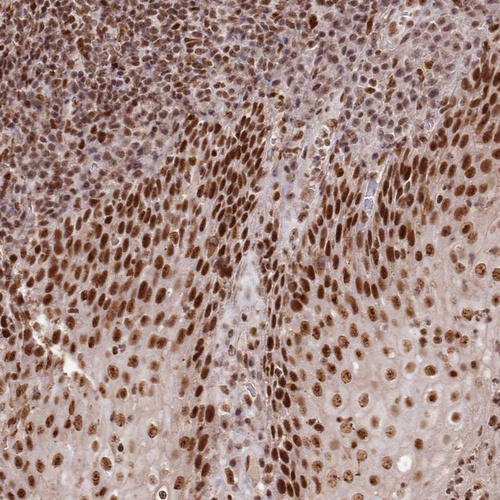

Immunohistochemical staining of human gastrointestinal, kidney, placenta and squamous epithelia using Anti-PDS5A antibody HPA036662 (A) shows similar protein distribution across tissues to independent antibody HPA036661 (B).